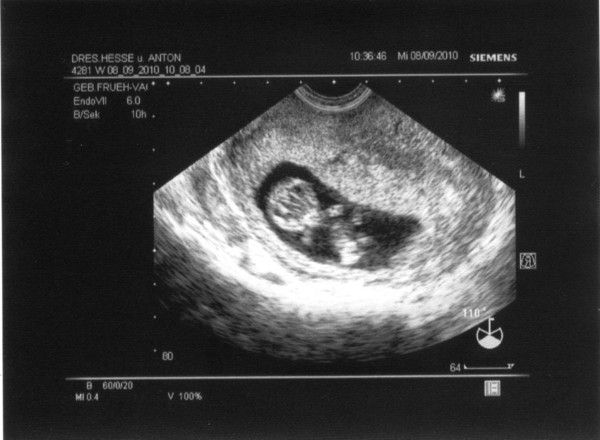

1.US_samulu_ET01042010

25.08.2010

zusehen ist schön der Embryo SSL 18mm; Markierung + ist Herzchen; rechts unten Nabelschnur und noch Dottersack

daraus ergibt sich eine Summe von ALLES OK in der 9.SSW (SSW8+5T)